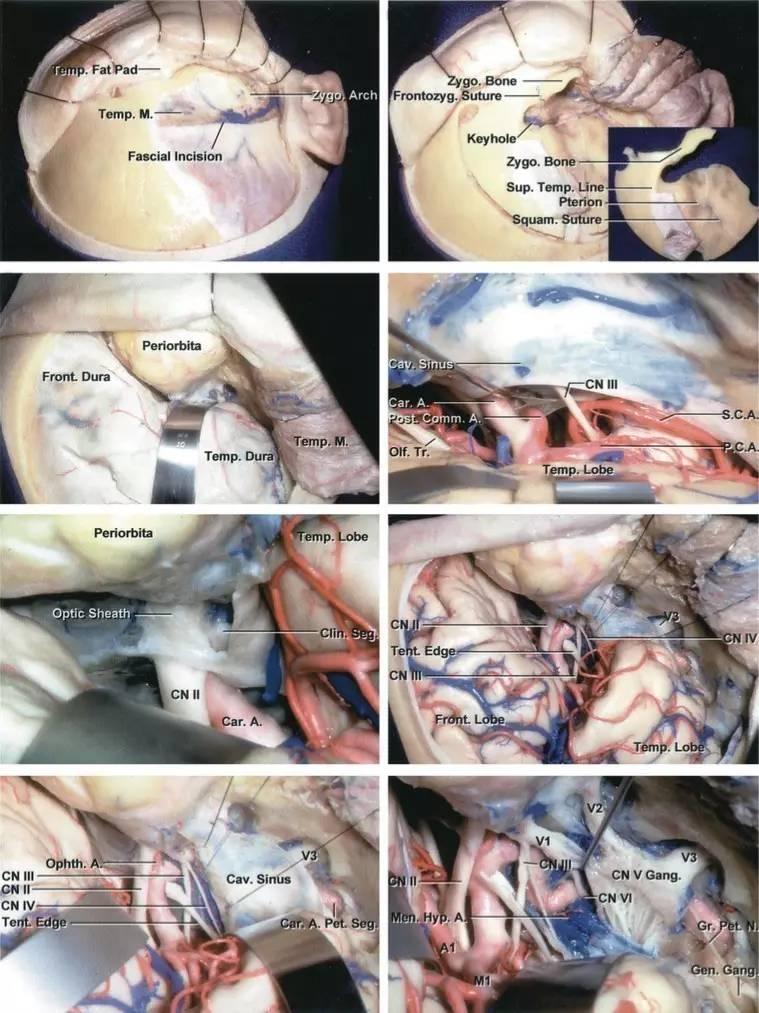

图4:海绵窦区的硬膜内入路解剖。大型肿瘤应联合硬膜内及硬膜外入路。(感谢Rhoton教授对图片的授权)

大多数海绵窦脑膜瘤的暴露最适合经眶颧开颅及硬膜外前床突切除术来实现。该入路灵活度大,可从多角度处理海绵窦,并可实现颈内动脉的近端及远端控制。

眶颧开颅时,患者取仰卧位,头部向对侧旋转30°。颈部区域需做好颈内动脉近端控制的准备。

掀起骨瓣后即可暴露眶内容物,肌电监测电极可直接置于上直肌、上斜肌、外直肌,以监测动眼、滑车、外展神经功能。